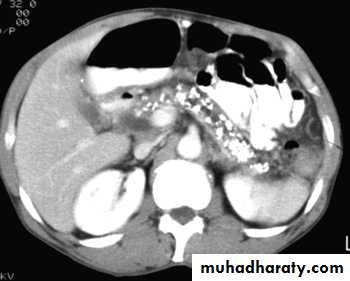

Acute pancreatitis

The pancreas is usually enlarged, often diffusely with irregular outlines due to extension of inflammatory process into the surrounding fat. There may be low density areas at CT or echo-poor areas at US (edema and necrosis)

The diagnosis is usually made on clinical and biochemical grounds, the purpose of CT is to assess the severity and complications:

1.pancreatic necrosis (areas with no enhancement)

2.abscess appear as fluid collection which may contain gas

3.vascular complications e.g. splenic vein thrombosis, arterial erosion & pseudoaneurysm

4.pseudocysts occur as a result of leak of pancreatic secretions that are contained in a cyst like manner within and adjacent to the pancreas.

They can be demonstrated with CT or US as thick or thin walled cysts of variable sizes.

Many pseudocysts resolve in the weeks following an attack of acute pancreatitis, some persist and may need surgical or percutaneous drainage.